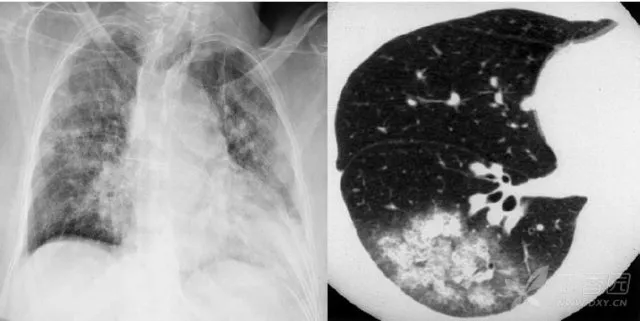

大葉性肺炎胸部影像

簡單來講,肺炎出現較大的病灶,局限在一個肺葉,就叫大葉性肺炎。大葉性肺炎也叫肺泡性肺炎,這是因為大葉性肺炎的炎性滲出主要發生在肺泡。細菌、病毒、真菌、以及肺炎支原體等非典型病原體都可以引起大葉性肺炎。